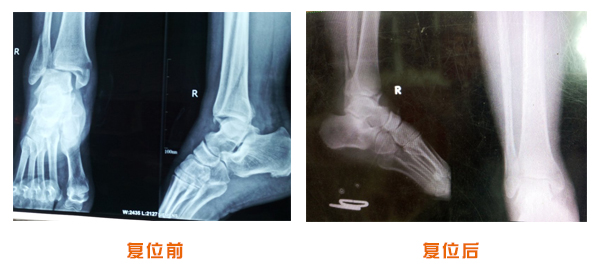

肥城市安駕莊梁氏骨科醫(yī)院是一所以梁氏手法正骨配合膏藥為特色的現(xiàn)代化專科醫(yī)院。

梁氏骨科術(shù)始創(chuàng)于清雍正年間,歷經(jīng)八代,至今已有三百年歷史。據(jù)1929年泰安縣志載“梁瑞圖先生,字增生,號(hào)蓮峰,安駕莊人,精岐黃并發(fā)明接骨,凡跌打車凡跌打車軋皮不破而碎骨者......【詳細(xì)】 |